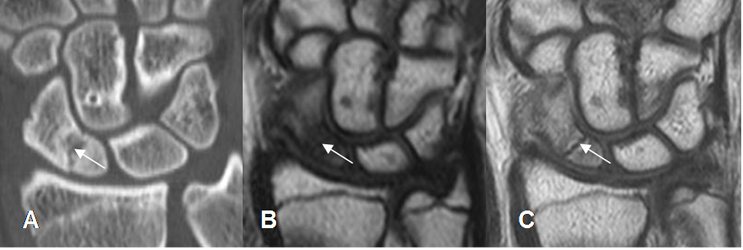

Fig 25. Osteonecrosis de escafoides.

A: TAC reconstrucción coronal. Fractura transversa en el tercio inferior del escafoides.

B: RM coronal en T1. El polo inferior del escafoides es mas hipointenso, lo que hace sospecha osteonecrosis.

C: RM coronal en T1 con contraste. El hueso escafoides presenta realce homogéneo, indicando viabilidad.